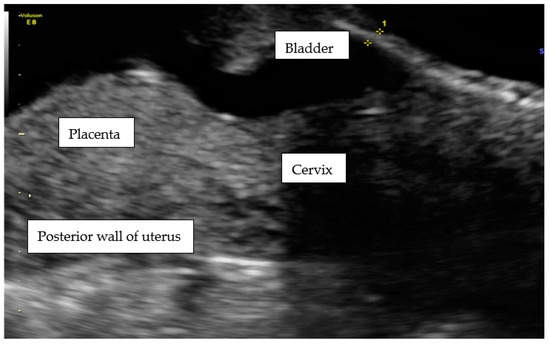

- 1

- an empty uterine cavity with clear endometrium and empty endocervical canal,

- 2

- the detection of a gestational sac within the anterior lower segment of the uterus embedded in the cesarean scar,

- 3

- an absent or thin (<5 mm) myometrium layer between the gestational sac and the bladder,

- 4

- 5

- the pathologies of the adnexa should be excluded, and there should be no detection of fluid in the Douglas pouch unless in the case of a massive hemorrhage or rupture of the uterus [5].